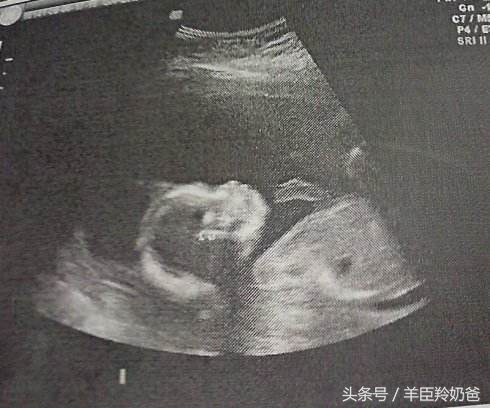

这个时期是做B超的最合适的时间,也是最重要的一次检查,在这个阶段可以通过B超检查胎儿的发育情况、能检查出胎儿是否有畸形,对胎儿的位置和羊水量也有一定的了解。